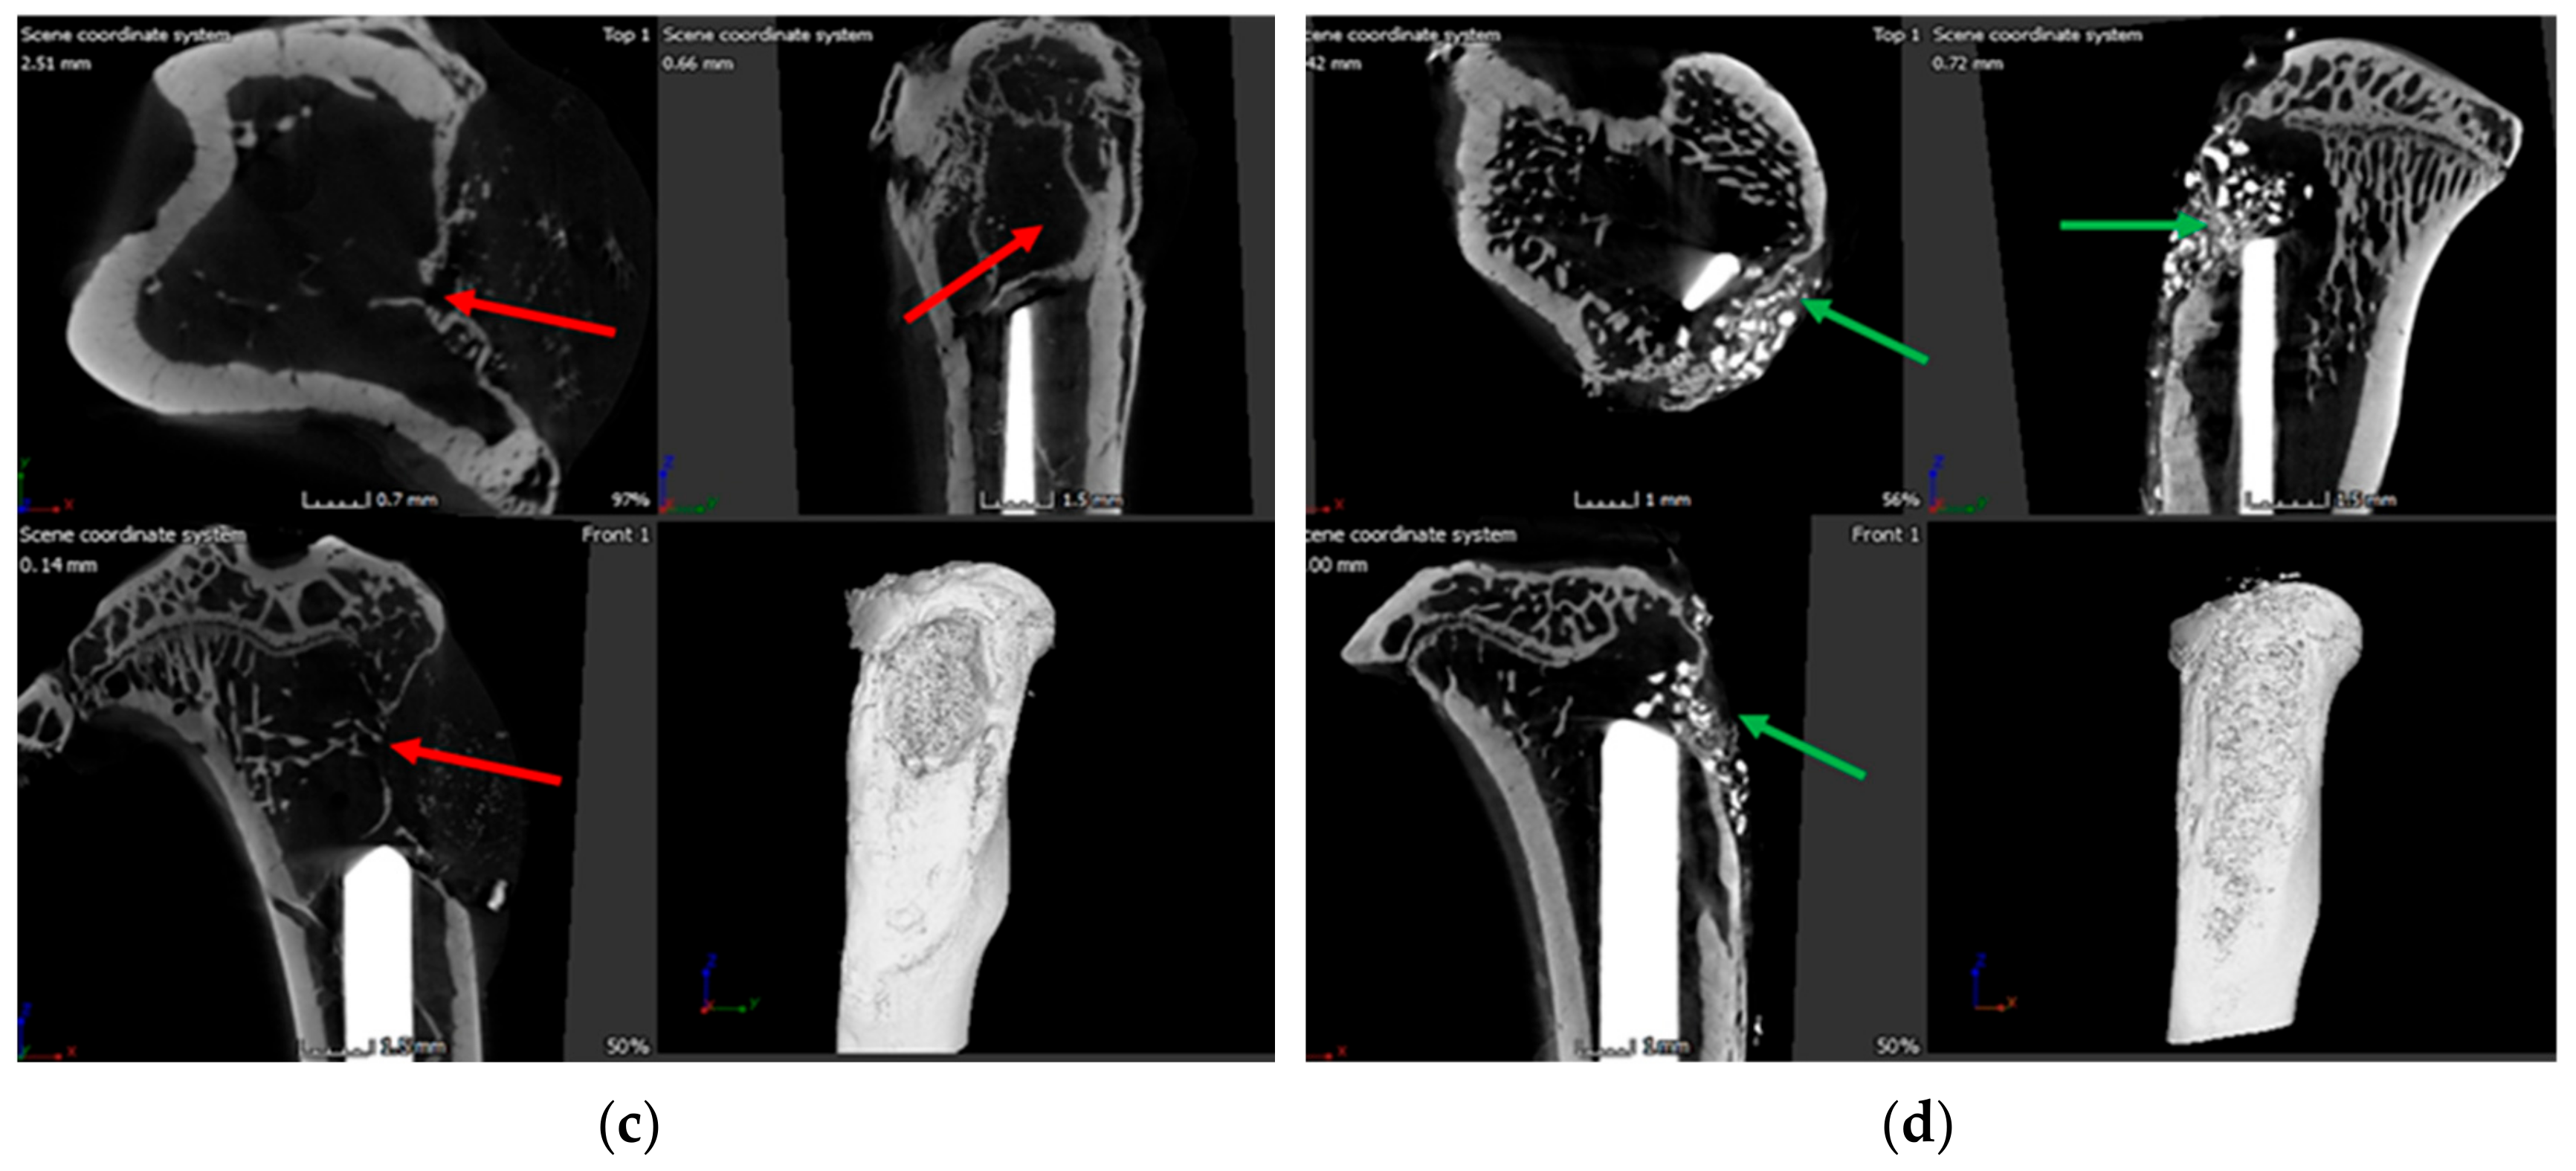

3.7. Bone Volume of Newly Formed Bone

3.8. Histology